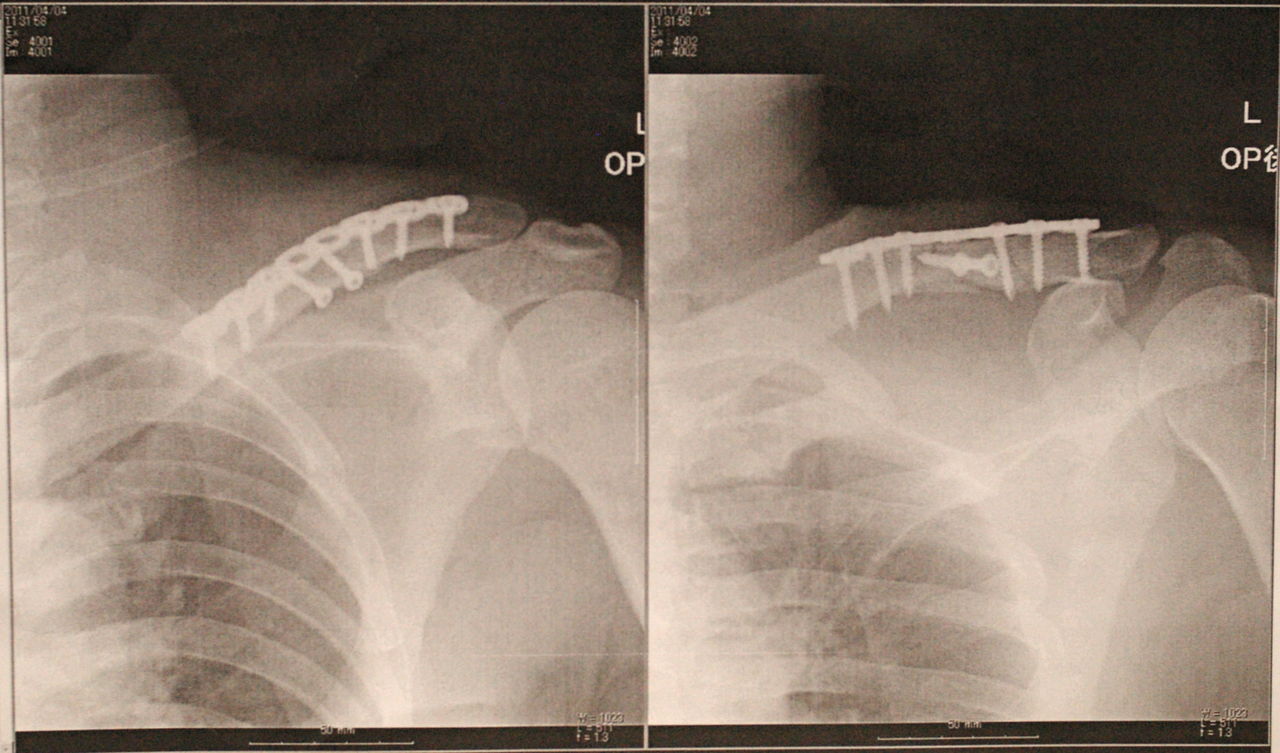

手術はなかなかの難工事だったようで、1時間で終わると言ってたのが2時間程かかったようです。まぁ、私は寝ていただけですが…。

大きくには4片に砕けた骨を8本のスクリューとプレートで止めています。

再来週抜糸して半年程このサイボーグ状態です。ということは早くて9月。スズカ大丈夫なのかなぁ。。。